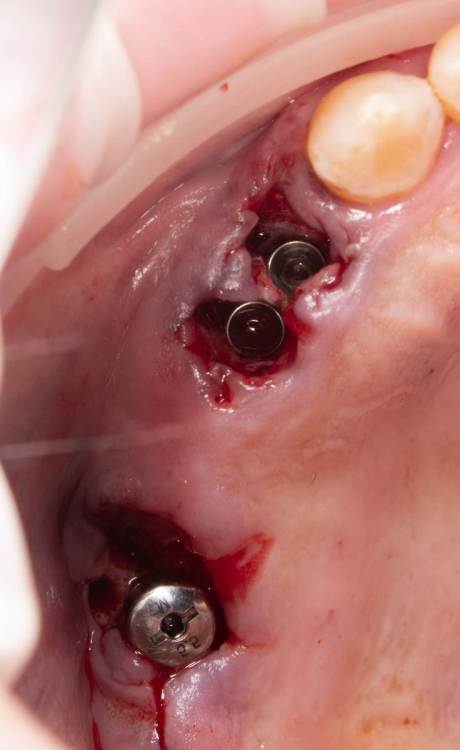

Женька Опубликовано 11 января, 2022 Автор Поделиться Опубликовано 11 января, 2022 Как я и говорил? купил объектив, теперь буду больше своих косяков фотографировать и выкладывать. Наконец-то руки дошли и машина доехала обратно до Башкирии и прооперировал пациента. Аккуратно сняли мост путём отпиливания по коронкам, удалили зубы достаточно быстро. Долго ловил пилотной фрезой дентиум правильное положение... так и не поймал. Вспомнил как Пётр Лазукин использует фрезу на турбинке для пилотного сверления и о чудо, сразу появилось устойчивое направление и линдеман перестал соскакивать, спасибо за видосики Петру Ну и далее по протоколу, пилотное положение 2.4 и 2.5 менял по 3 раза каждый (а в итоге всё равно не доволен получившимся направлением и судя по всему слишком близко) 2.7 с синуслифтингом. В лунки A-oss, сверху мембрана от Владмивы. И заживление через 9 дней. К сожалению, фото швов и той порнографии, что была сделана с лунками и мембраной нет. Резюмируя, это были 35-38 имплантаты которые я поставил, я уже чувствую себя намного увереннее (когда как Пётр турбиной пилотную точку сделал вообще в себя поверил ), но проблемы с позиционированием ещё долго будут меня преследовать. Жду критику и помидоры за РГ контроль. Ссылка на комментарий